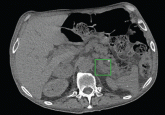

ArticleA 61-year-old man with fluctuating hypertensionAuthor:Razvan Chirila, MDPublish date: November 1, 2014In this patient with diabetes, an episode of hypoglycemia led to an unexpected discovery.Read More